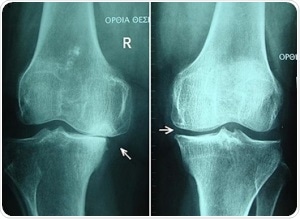

Knee osteoarthritis stages II and III by Harrygouvas at Greek Wikipedia. [CC BY-SA 3.0 or GFDL 1.3], from Wikimedia Commons

Osteoarthritis is a common degenerative condition. It is characterized by the diminution of cartilage in and around the joints which results in pain and loss of mobility. Age is seen to be the most common cause of osteoarthritis, but, traumatic joint injury can also cause joint degeneration in people of all ages. The progression of the condition can be slowed and symptoms can certainly be managed, however the underlying causes that lead to the development of this condition cannot be reversed.

Recent studies on osteoarthritis have led to the belief that changes to the subchondral (below the cartilage) bone structures, like thickening of the subchondral plate, are apparent prior to lesions or other symptoms becoming obvious in the cartilage itself.

The current standards giving recommendations on the diagnosis and treatment of osteoarthritis depend on radiographic imaging to detect either of two things. First, the hardening of the subchondral layer, or second, a reduction in joint space and visual and tactile inspection during arthroscopic surgery.